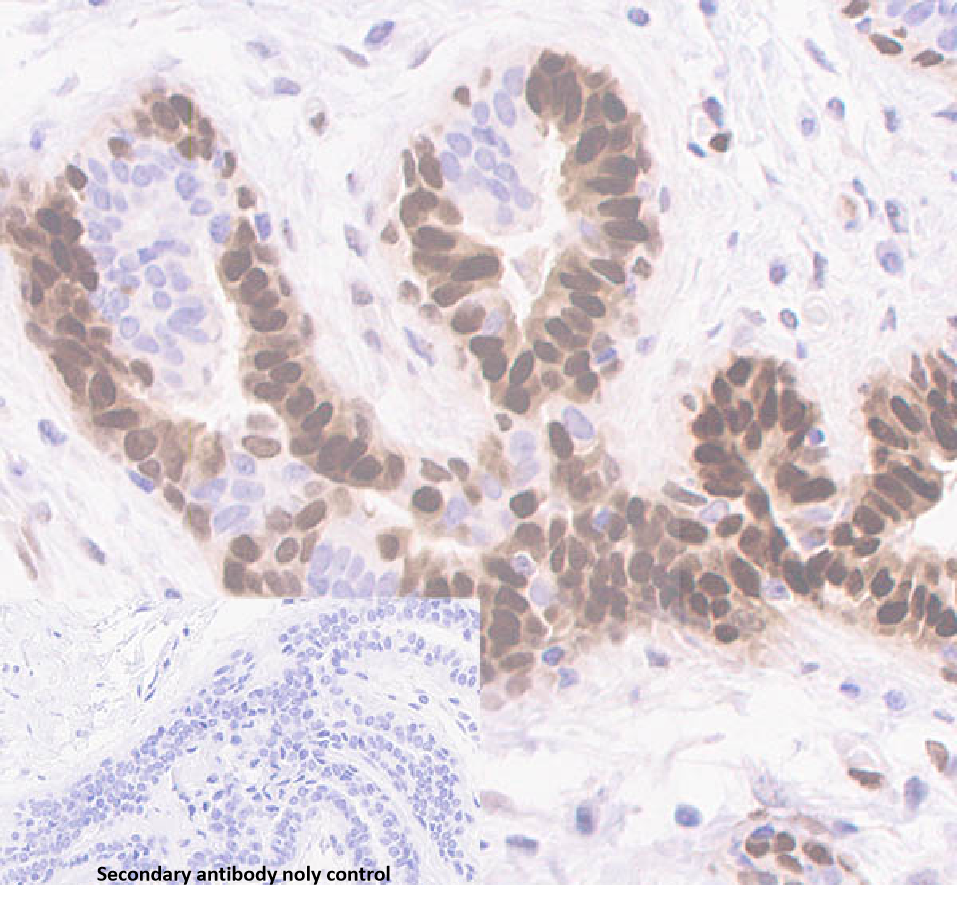

Basic Fibroblast Growth Factor b-FGF is a peptide-producing factor that functions as a cell growth inhibitor and is mainly used in prostate, pancreatic, and breast cancers.

The b-FGF Antibody Reagent binds specifically to the b-FGF molecular antigen. Immunohistochemistry kits containing the b-FGF Antibody Reagent are suitable for the precise diagnosis of prostate, pancreatic, and breast cancers.